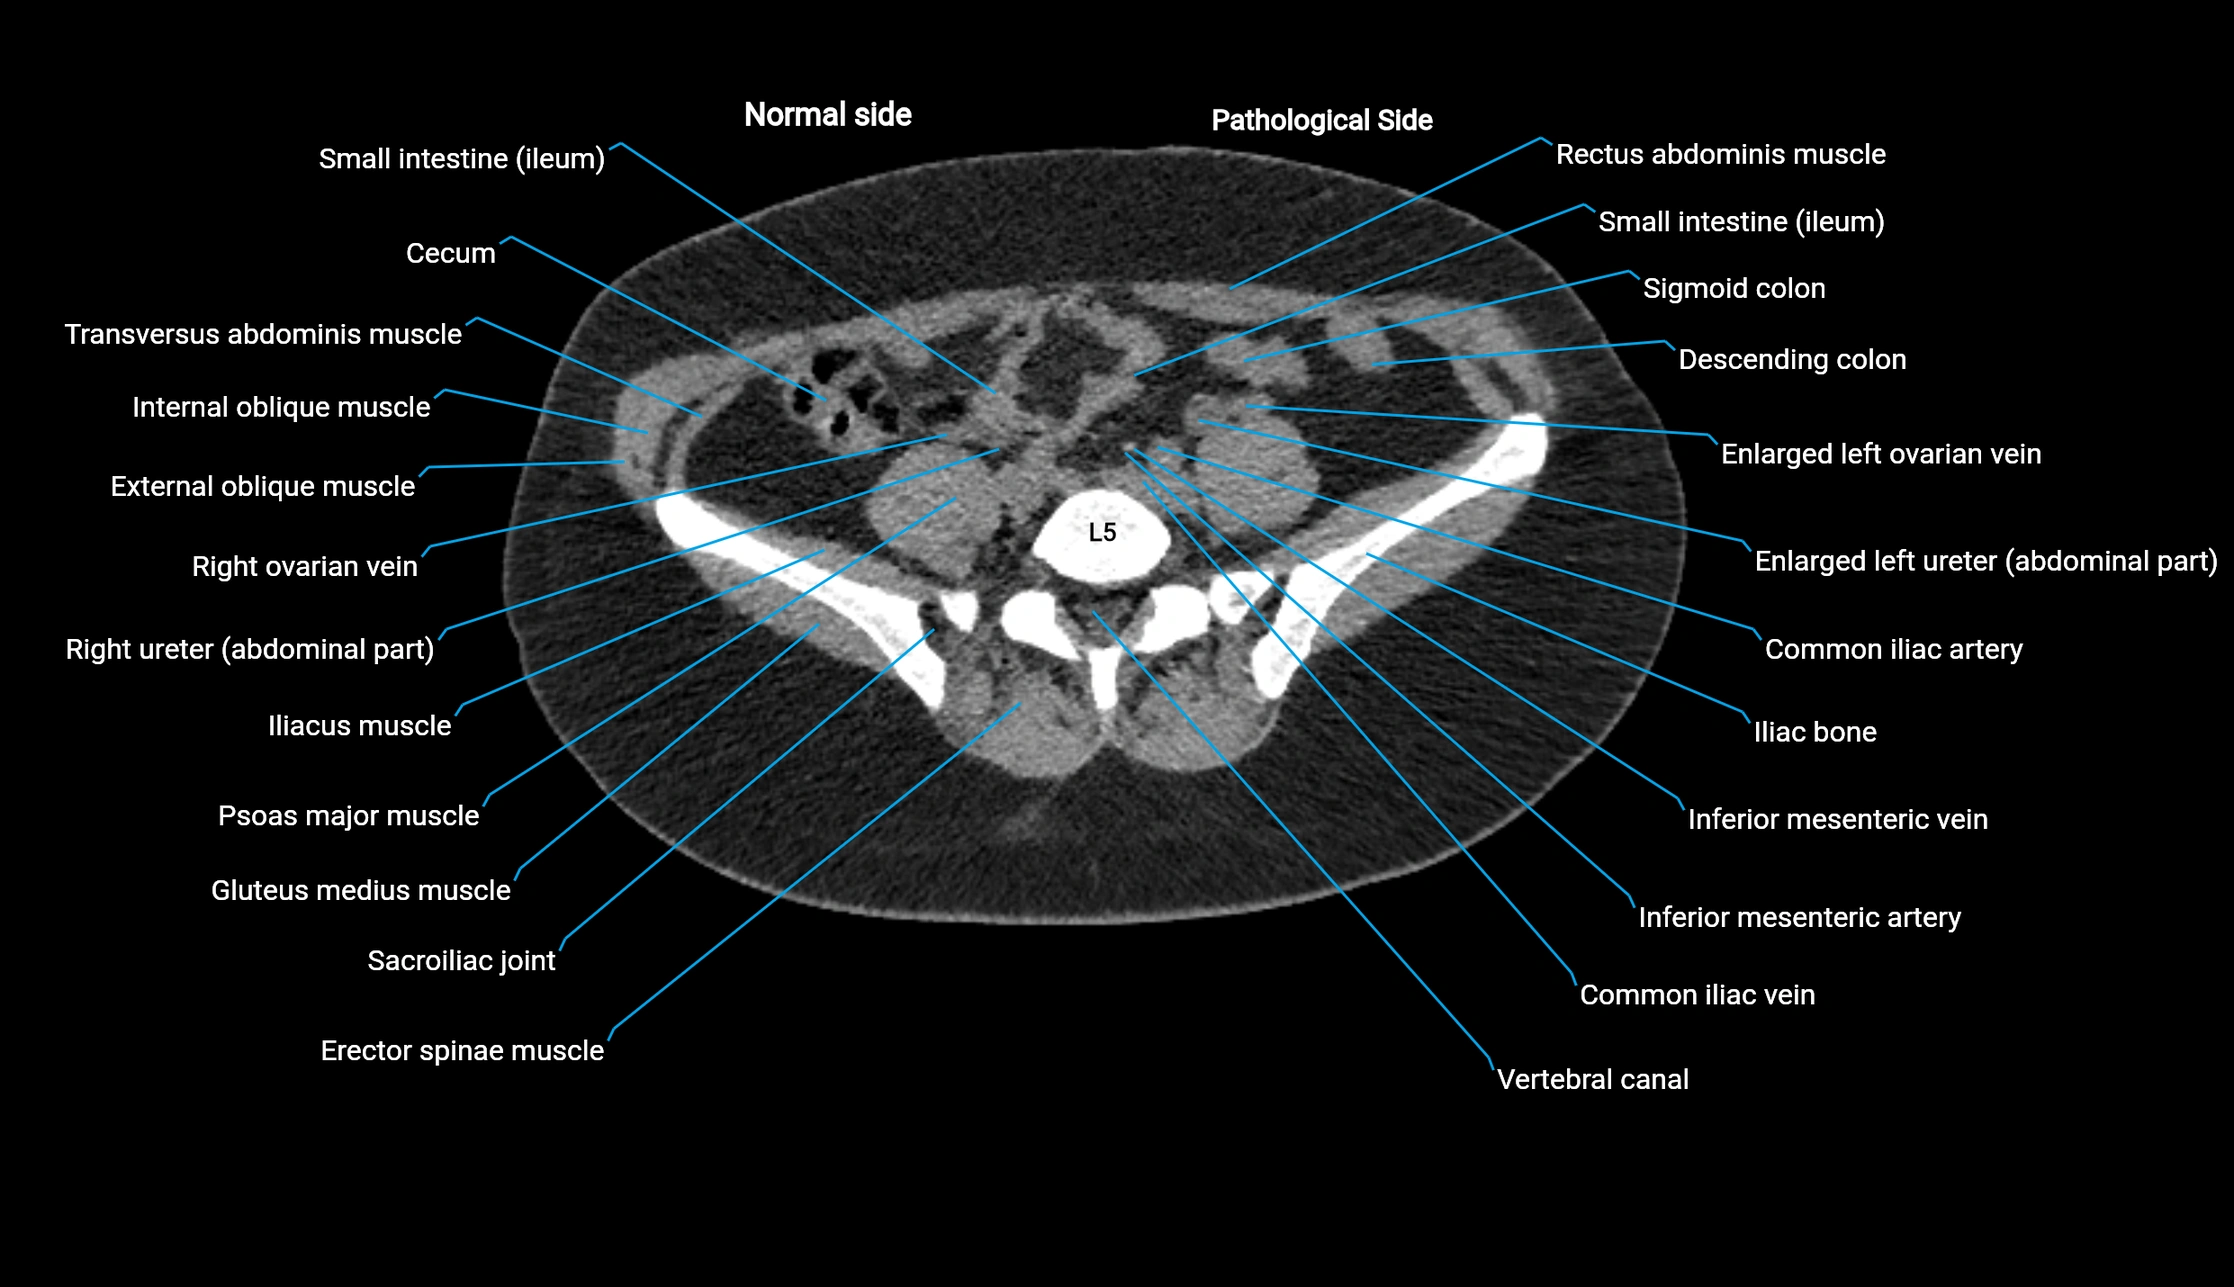

CT image

image